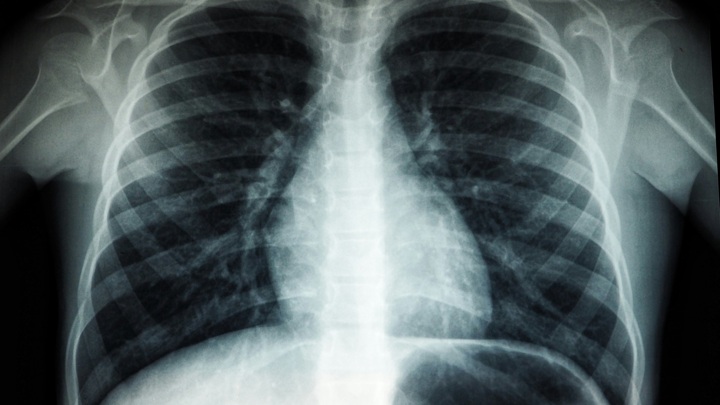

Диагностика EVALI: как выявляют

Чтобы установить диагноз, специалист собирает анамнез: уточняет, как давно развились симптомы, пользуется ли пациент вейпами, и если да, то какими жидкостями. Также проводится аускультация легких (прослушивание), — чтобы выявить хрипы и оценить частоту дыхания.

Также проводится рентгенография грудной клетки. Рентген часто показывает двусторонние инфильтраты (затуманенные участки) — признаки воспаления в легких. Если же исследование недостаточно информативно (а так бывает часто из-за низкой чувствительности теста), также выполняют компьютерную томографию (КТ), которая показывает очаги воспаления и участки утолщения интерстициальной (соединительной) ткани.